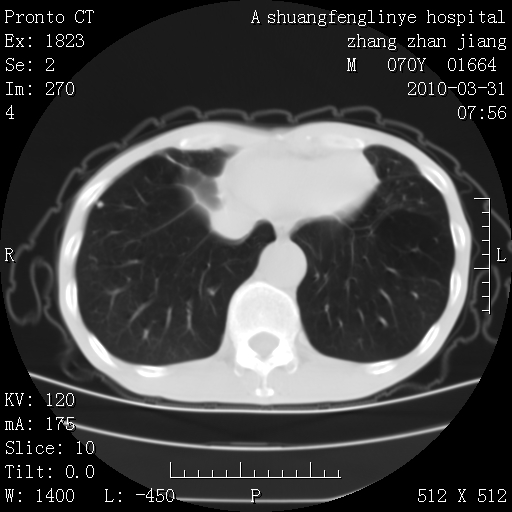

双上肺继发型tb并左上空洞形成,主动脉冠脉钙化。

1)两肺上叶继发性肺结核并左肺上叶空洞形成。2)冠状动脉及主动脉钙化。